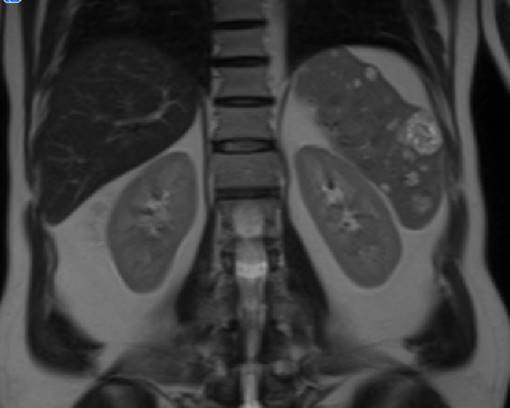

Solicitamos resonancia de abdomen que informó lesiones esplénicas múltiples, desde puntiformes hasta de 35 mm, que realzan heterogéneo con el contraste intravenoso (figura 2) (figura 3).

Figura 3: Resonancia magnética abdomen. Corte coronal. Lesiones esplénicas múltiples.